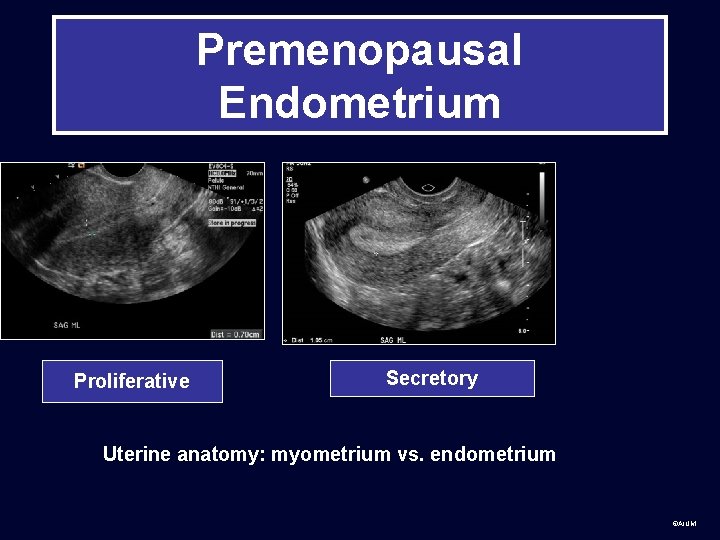

Premenopausal Endometrium Proliferative Secretory Uterine anatomy: myometrium vs. endometrium ©AIUM